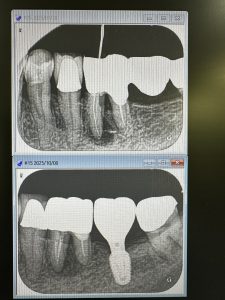

8ヶ月後の変化

欠損部には支柱になるワイドインプラント

だいぶ分岐部が改善されてきている💪

病巣も!

半年後の定期検査が楽しみだ🤪